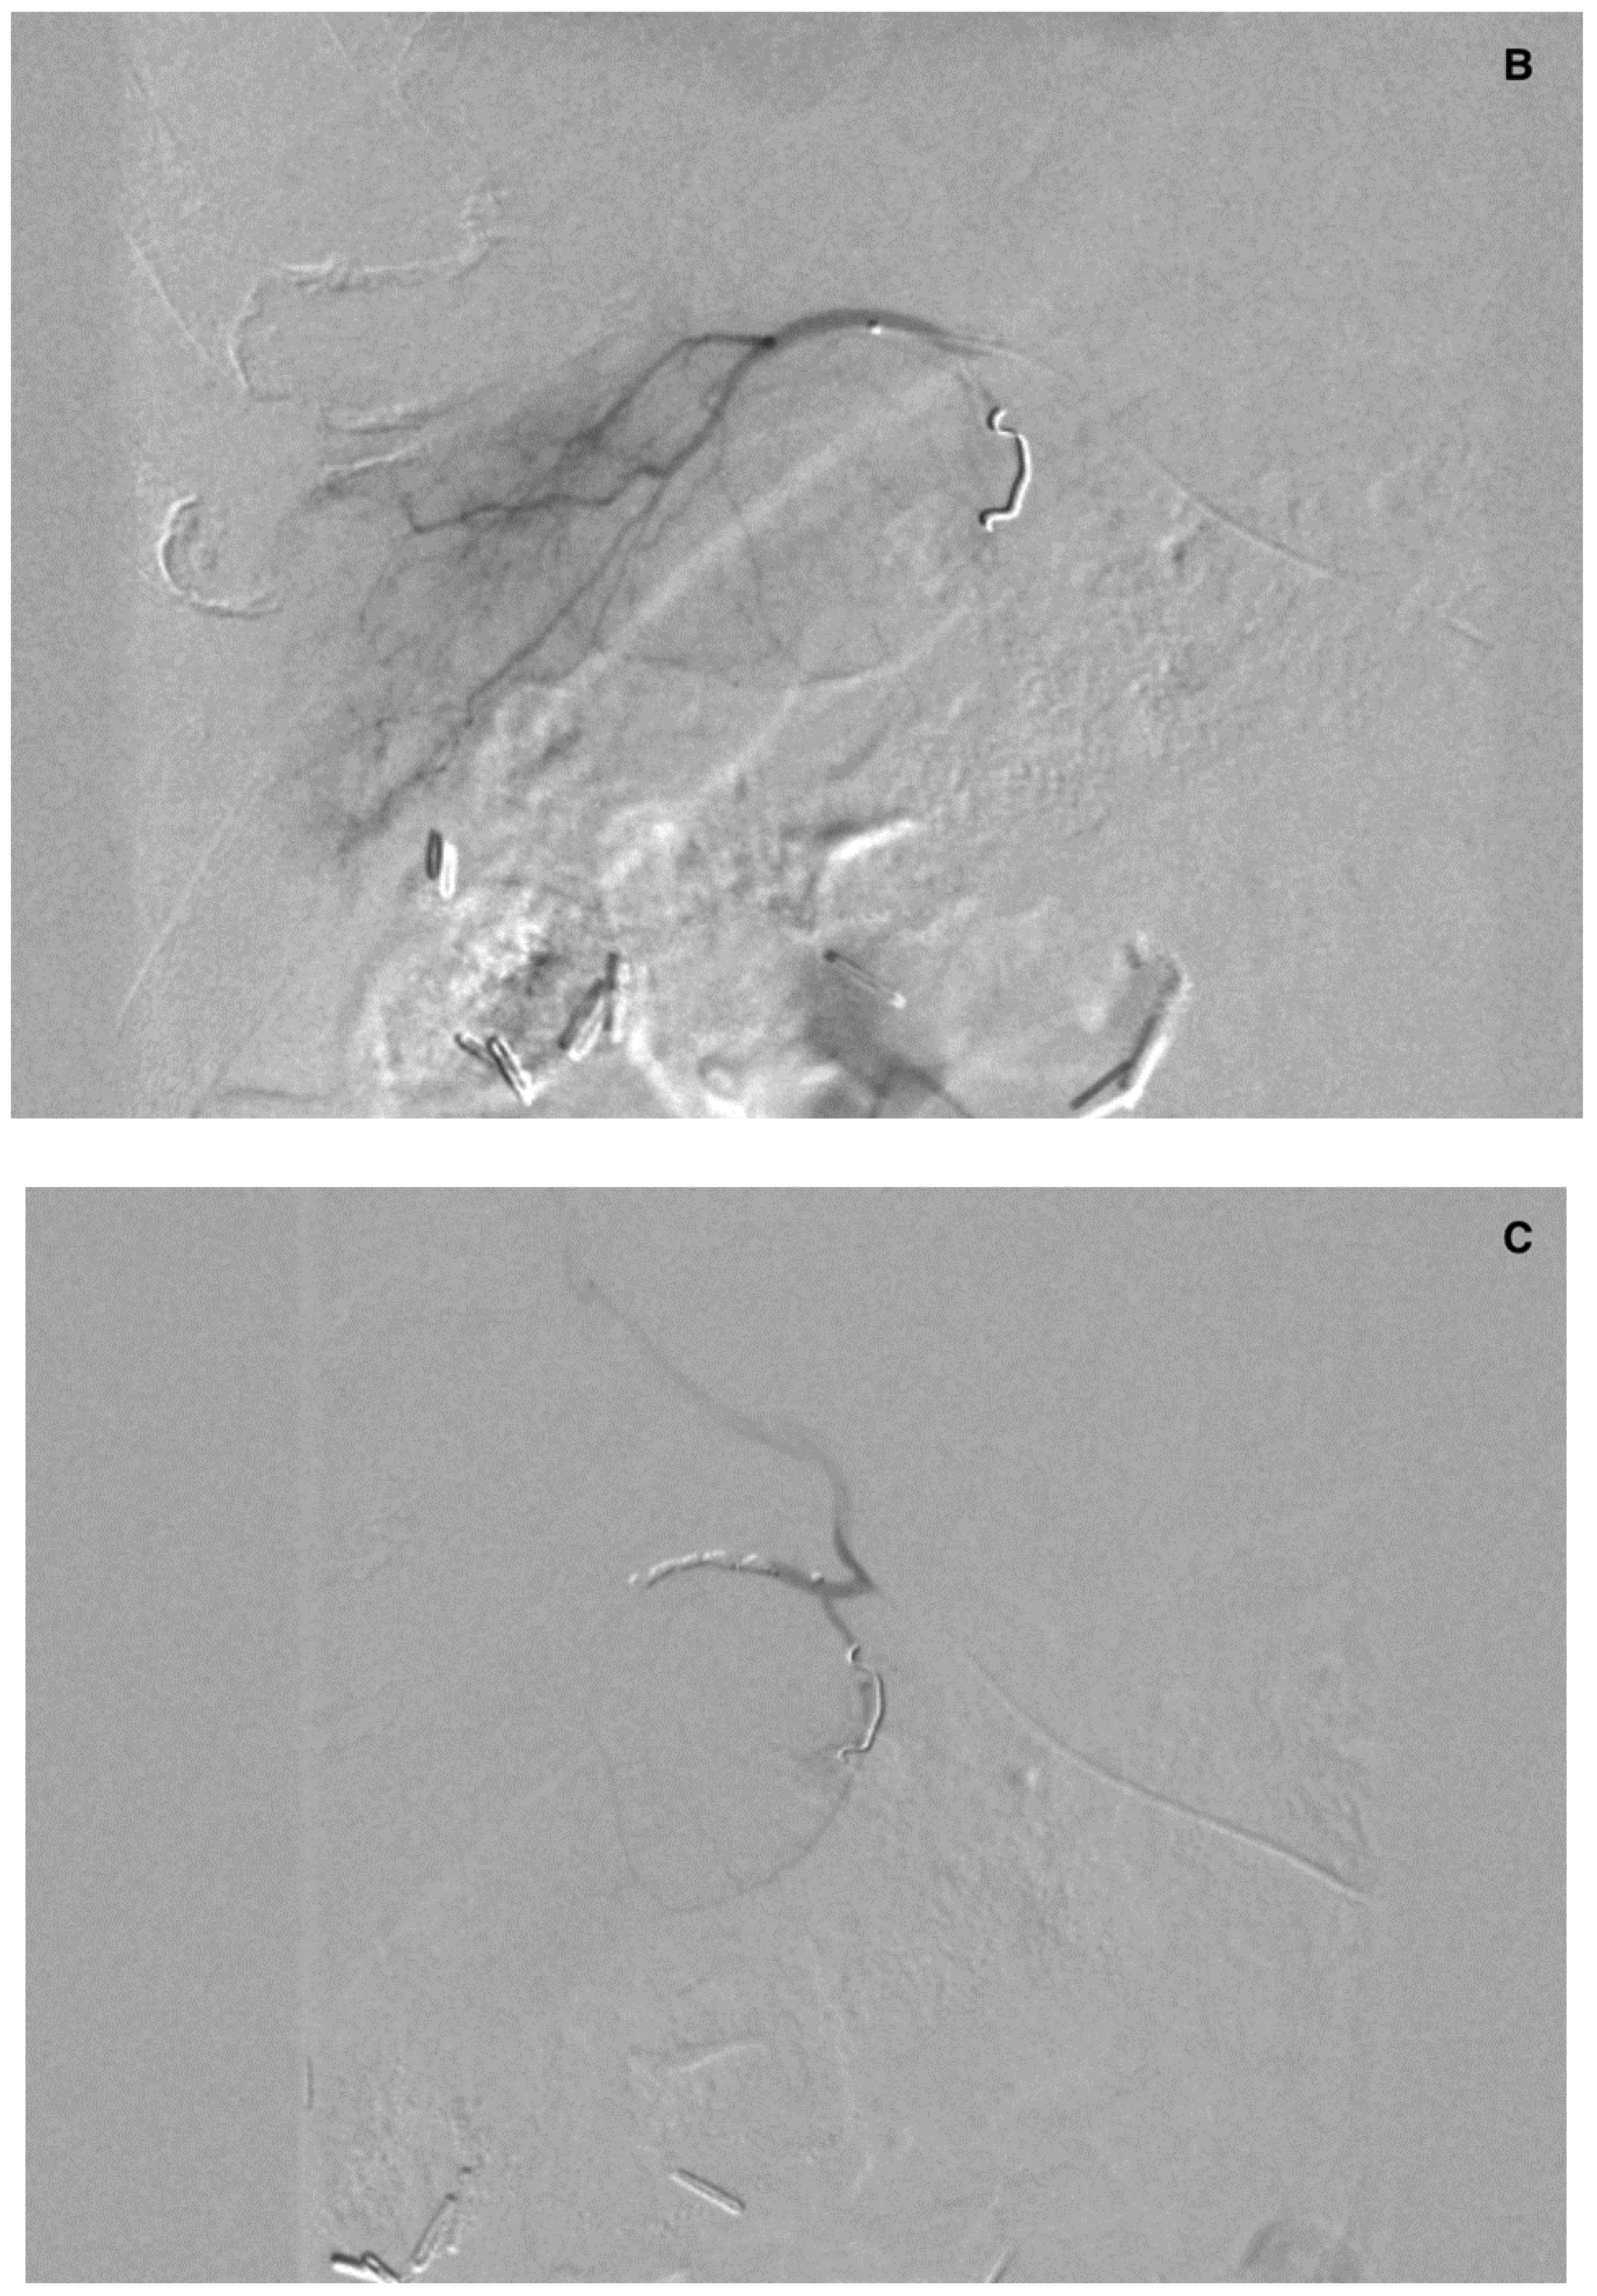

There were 20 patients after cholecystectomy. There were 30 (40%) patients with additional cystic arteries (Figure 3).

Figure 3.

Angiogram of the right hepatic artery. (A) Initially, single CA is visible (arrows) originating from the right hepatic artery division. (B) After embolization, another artery reveals multiple intrahepatic anastomoses to the gallbladder wall, and needs to be embolized. (C) There is insufficient embolization of both CA, and (D) retraction of the microcatheter reveals another CA originating proximally to the right hepatic artery division (arrows).

Mean distance of the right hepatic artery division from the cystic artery was 4.7 mm (0–35, 6 mm). The cystic artery originated from the right hepatic artery division in 14 patients.